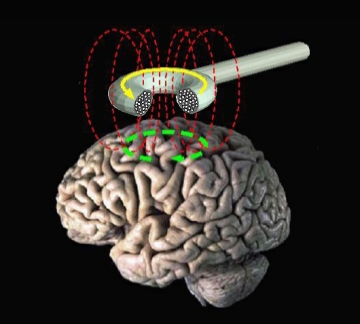

Another common form of therapeutic brain stimulation is non-invasive, but only moderately specific. Transcranial Magnetic Stimulation, or TMS, uses magnetic fields to stimulate electrical activity in the brain without requiring any surgery. However, to produce a strong enough magnetic field, you need a large, expensive machine. Thus patients must come in for periodic treatments, and DBS-style constant stimulation is not an option. While TMS is much more specific (and much less scary and controversial) than electroconvulsive therapy (ECT) — which is still used in extreme cases and essentially induces a seizure in the whole brain — it is unable to stimulate a deep brain region without also affecting much of the brain areas surrounding it. Studies have shown that TMS treatment on prefrontal regions of the brain can effectively alleviate depression, leading to its FDA approval for this application in 2008. How exactly magnetizing the brain relieves depression is still poorly understood, but it is thought to more or less “reset” the systems of the brain and re-establish connections responsible for mood [7]. (For more detail on brain stimulation therapies see this page from the National Institutes of Mental Health)

Diagram of the magnetic field produced by a TMS device.